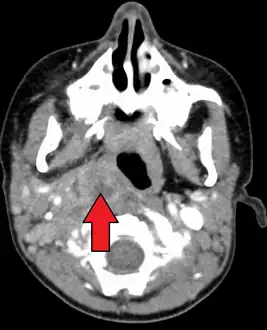

Large retropharyngeal abscess as seen on CT

Large retropharyngeal abscess as seen on CT Large retropharyngeal abscess as seen on CT

Large retropharyngeal abscess as seen on CT

A computed tomography (CT) scan is the definitive diagnostic imaging test.[4]